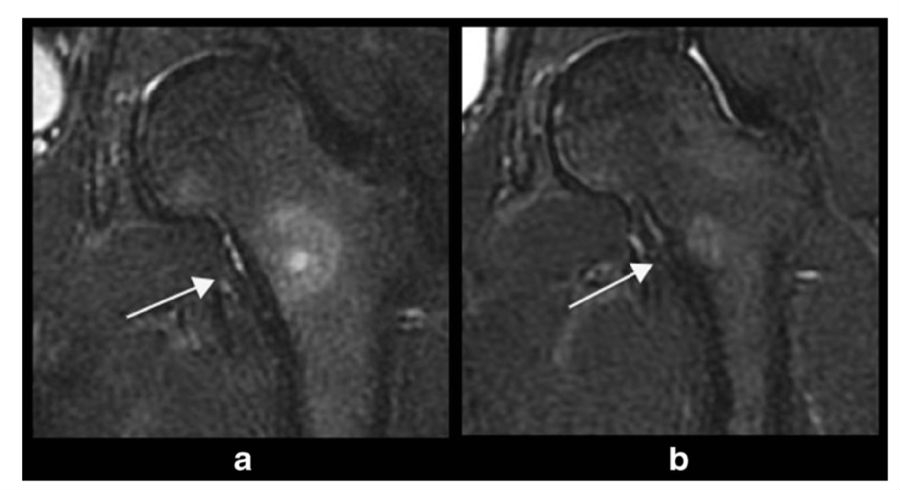

因为骨样骨瘤病灶小、局限,适合热消融治疗的特点,Geiger等将MRgFUS应用于骨样骨瘤的治疗,该项多中心临床研究报道了29例非脊柱骨样骨瘤病例,临床完全缓解率达到90%,10%的患者达到部分缓解,治疗前后VAS评分显著下降[17]。Masciocchi等对比了MRgFUS与RFA的疗效,发现两种治疗方法的临床完全缓解率接近(MRgFUS 94%与RFA100%),证明了无创的超声消融可以获得确切的疗效[18](图2)。

图2. 磁共振引导聚焦超声消融骨样骨瘤病灶